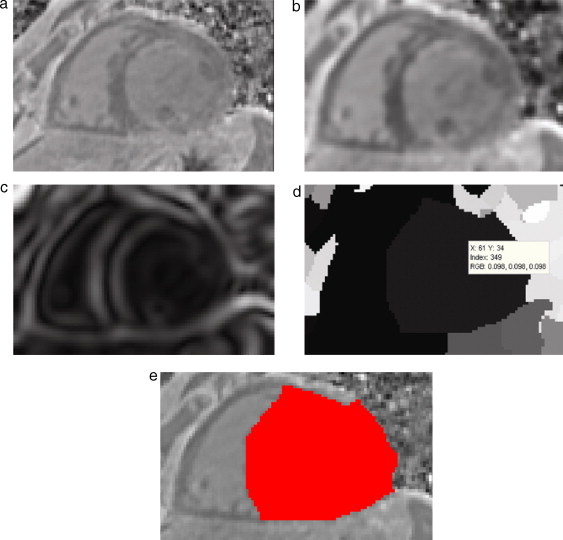

Para conseguir reducir el ruido de las imágenes sin atenuar las zonas de interés y resaltar adecuadamente las estructuras que conforman el corazón se necesitaba de una técnica de filtrado con preservación de bordes. El filtro de difusión anisotrópica comentado en el apartado 2.2.1 resultó ser ideal para este tipo de tareas. Como siguiente paso, se aplicó el cálculo del módulo gradiente sobre la imagen filtrada, lo cual permitió diferenciar de mejor manera los contornos de las estructuras del corazón.

3.1.2. Segmentación

Segmentar el volumen del ventrículo izquierdo puede resultar una tarea no tan complicada si se combinan técnicas de segmentación adecuadas para extraer estructuras grandes y bien definidas. En este caso, se obtuvieron mejores resultados al combinar dos técnicas de segmentación muy utilizadas en este tipo de tareas. En primer lugar se aplicó el algoritmo Watershed en la imagen gradiente, obteniéndose una imagen en escala de gris con las regiones uniformes etiquetadas por una intensidad de gris diferente para cada segmento obtenido. Watershed tiene la desventaja de producir sobre-segmentación si es aplicado sobre imágenes ruidosas y niveles de gris poco uniformes, sin embargo, esta dificultad fue superada al aplicar esta técnica sobre la imagen preprocesada. Posteriormente se utilizó la técnica de umbralización para determinar el umbral (o umbrales) que conforman la zona del ventrículo izquierdo, entre el conjunto de segmentados etiquetados.

En la figura 15 se presentan los resultados obtenidos por cada etapa de procesamiento en IRM cardiovascular. Las imágenes médicas utilizadas tienen formato DICOM [39] , con 59 cortes de tamaño 192 × 192 pixels, voxel spacing: 1,5625 × 1,5625 × 2,5 mm . Por efectos de visualización, solamente se presenta uno de los cortes axiales de la imagen 3D.

Figura 15. Preproceso y segmentación el volumen del ventrículo izquierdo. (a) Corte axial de la IRM cardiovascular original. (b) Imagen (a) filtrada con difusión anisotrópica. (c) Imagen gradiente obtenida a partir de (b). (d) Imagen Watershed con segmentos etiquetados obtenida a partir de (c). (e) Selección del segmento del ventrículo izquierdo empleando umbralización. |